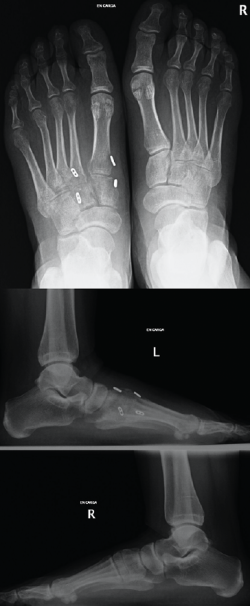

La revisión a los 3 meses mostró resultados satisfactorios en ambos casos, con tolerancia de la carga completa. Además, las imágenes radiológicas demostraron el mantenimiento de la reducción conseguida en el quirófano, sin movilización del material (Figuras 5 y 6).

Figura 5. Resultados radiográficos posquirúrgicos en el caso 1.

En el primer caso, la incorporación laboral fue a los 4 meses y, en el segundo caso, a los 6 meses; los pacientes no presentaron dolor. A los 10 meses postoperatorios el examen clínico no reveló evidencia de dolor en la zona quirúrgica y los pacientes habían reanudado todas sus actividades regulares, incluida la práctica deportiva, sin complicaciones. Además, las radiografías en ese momento revelaron una reducción anatómica de la lesión.